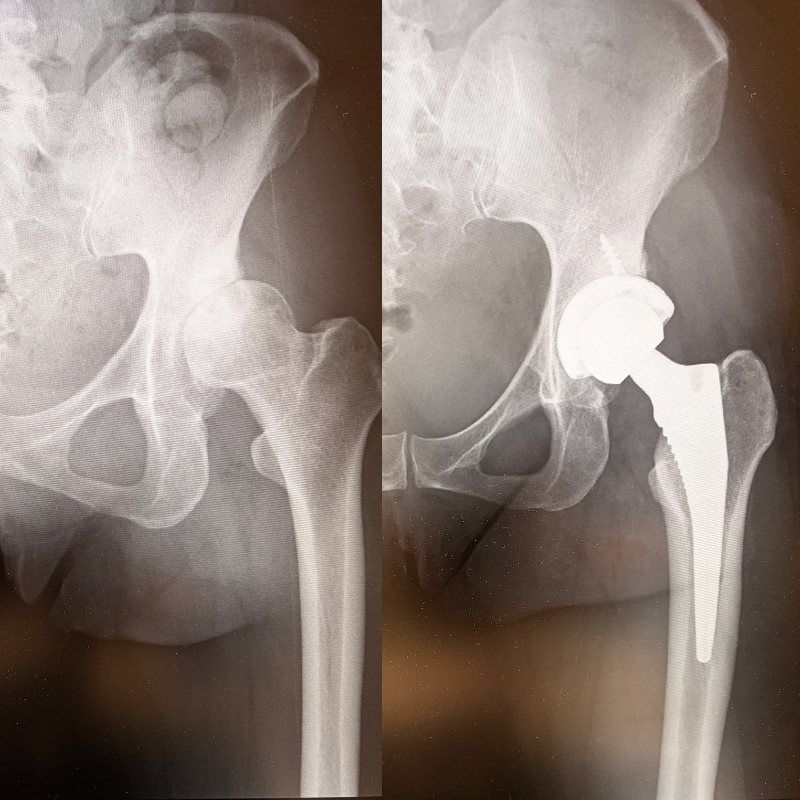

手術ビフォー・アフター(40代女性の例)。ビフォー(左)は臼蓋形成不全のため臼蓋のかぶりが浅く、さらに関節軟骨がすり減り、歩くのもつらい状態(囲み部分)。アフター(右)は人工股関節が入って1年後の状態。海外旅行にも行けるまでになり、骨密度もアップしたという